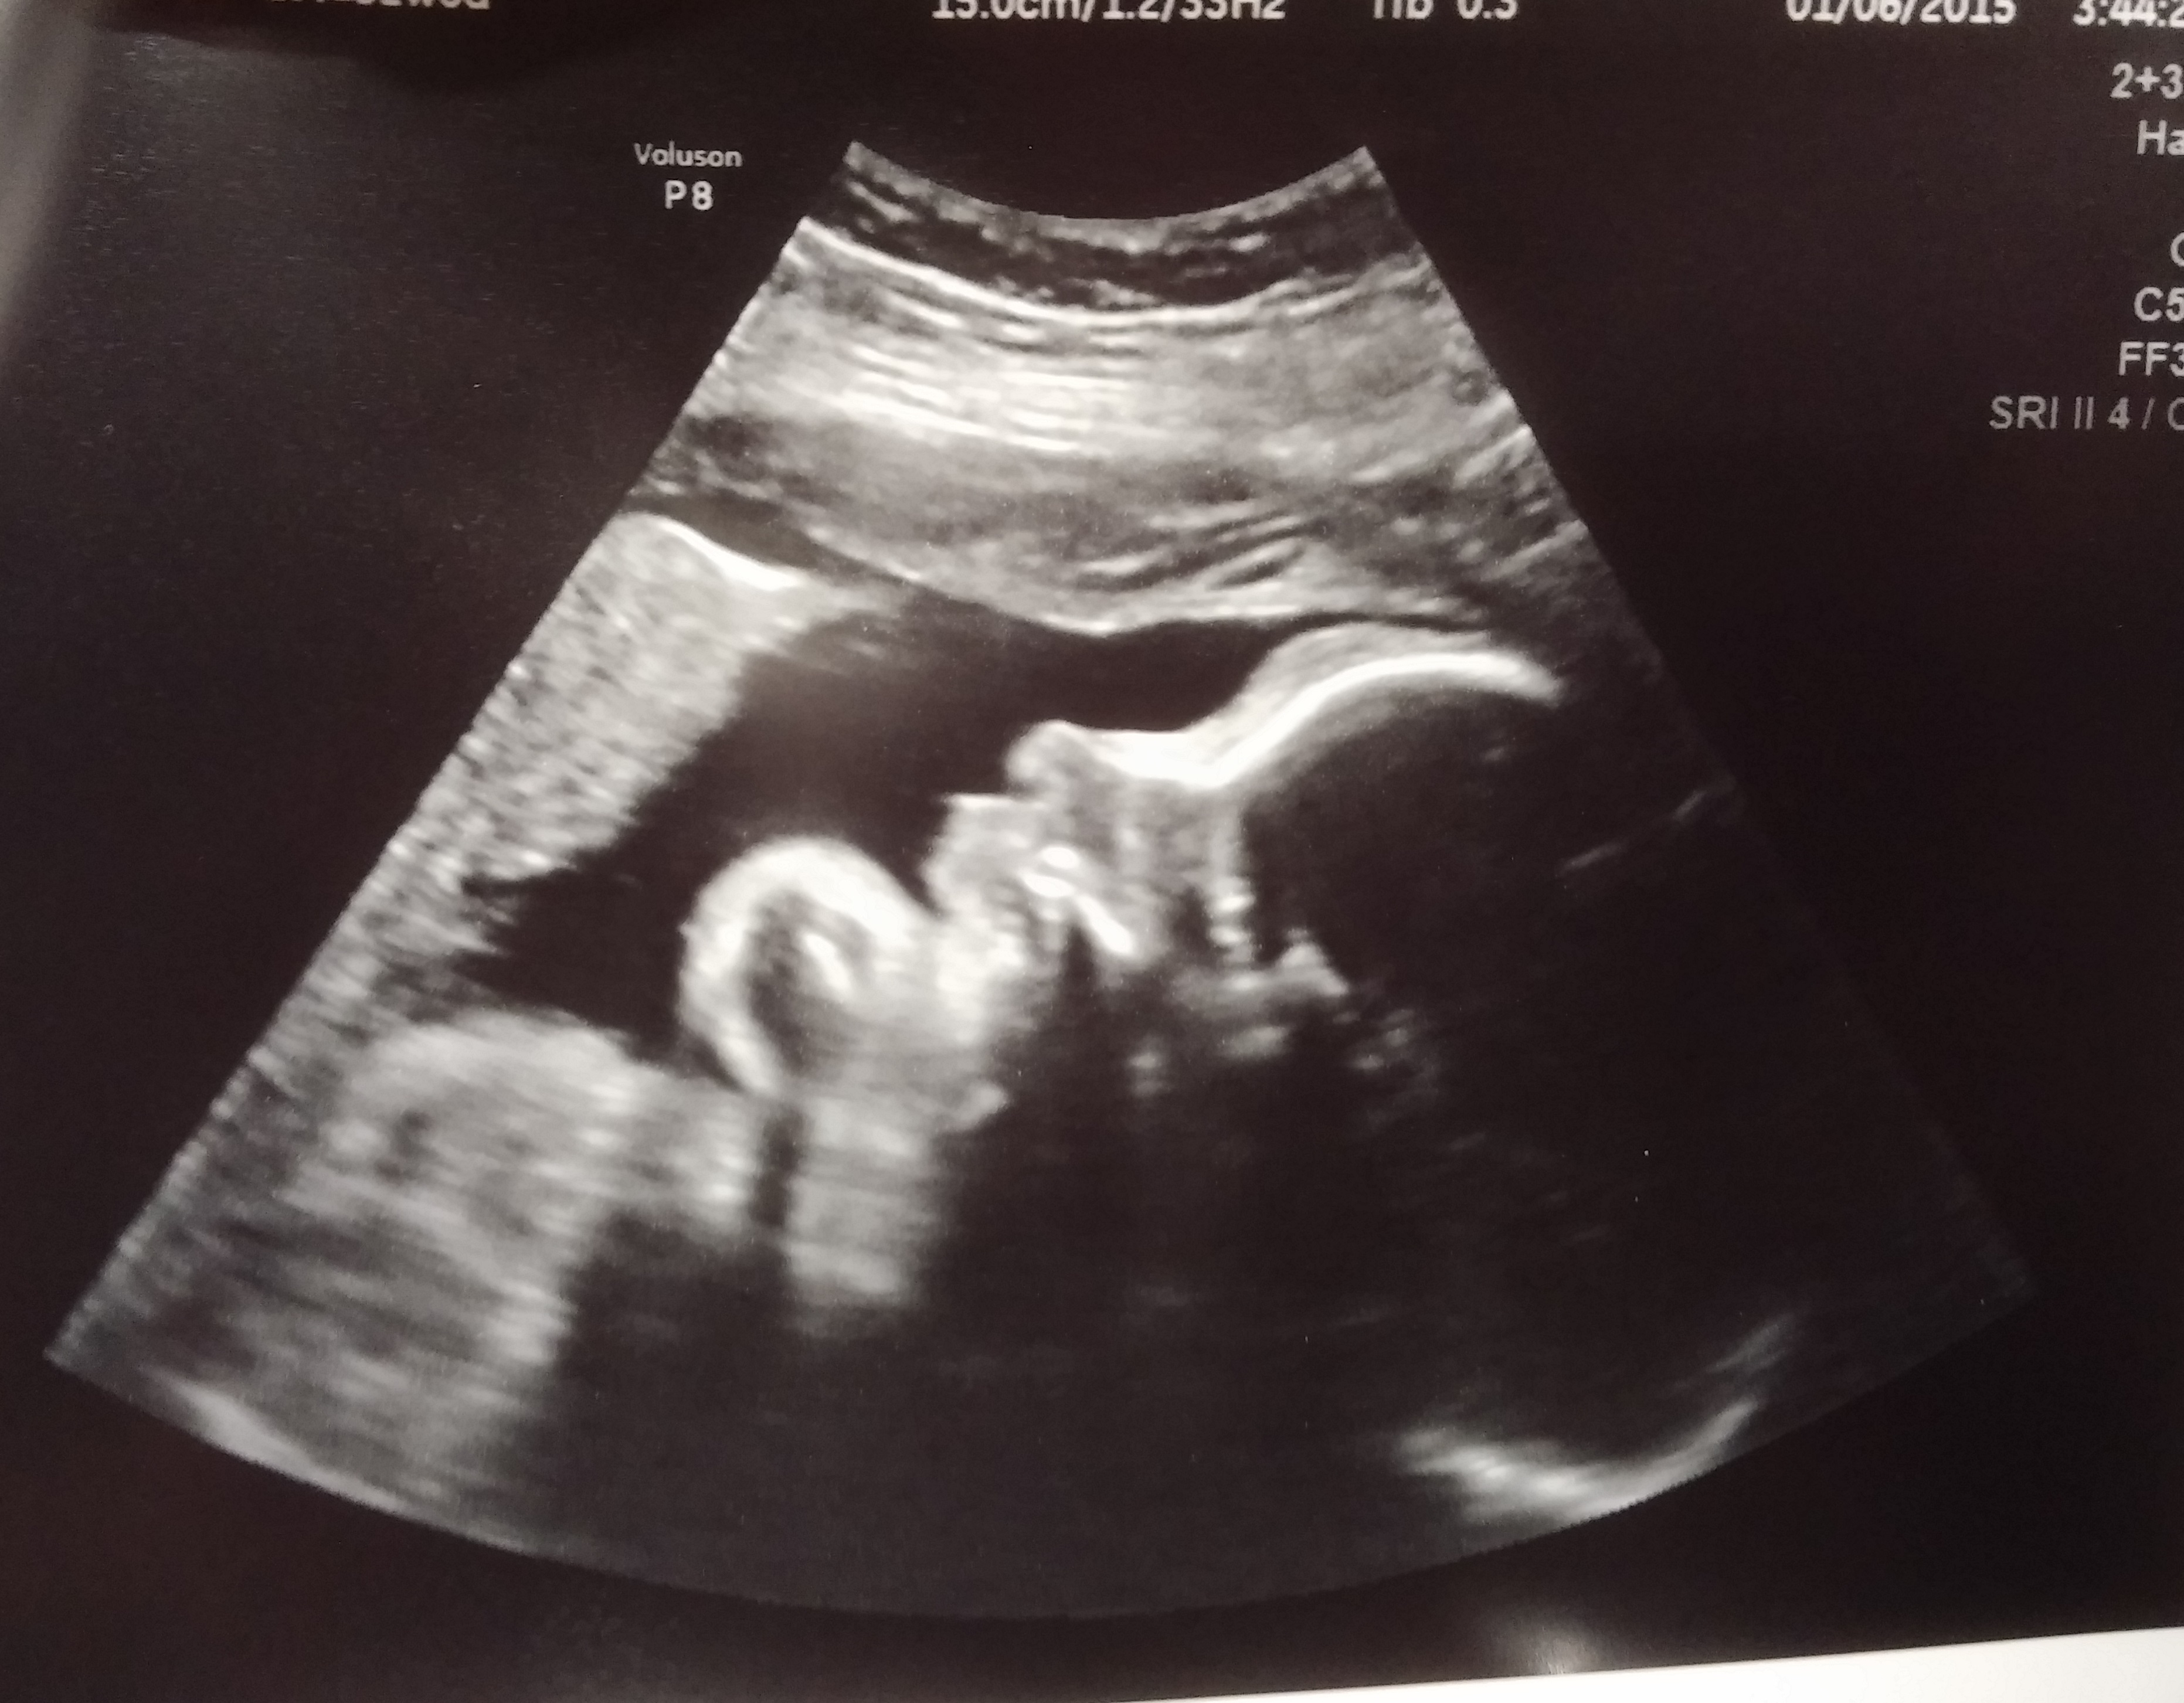

But I do have some good news everyone!

Cervix is holding steady and placenta has moved!! So baby will likely go to term and I will deliver normally.

She is measuring a week ahead so my adjusted due date is march 6th.

She's 4lbs 4oz with a strong heartbeat and a strong will :P

Thanks for all the well wishes and prayers. They are working!